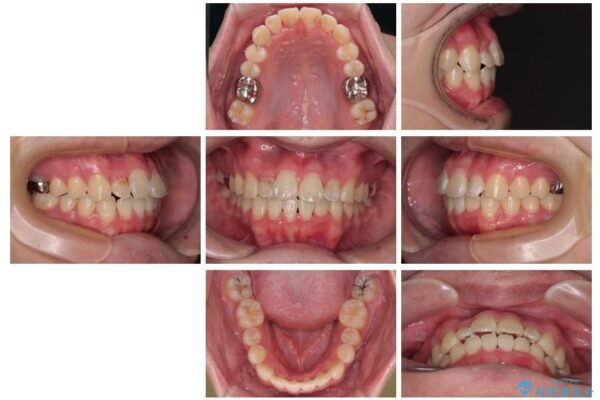

「歯並びがデコボコしていて、上下の中心がズレているのが気になる…」という悩みで来院された患者さまの症例をご紹介します。

初診時の状態

・上下ともに歯がきれいに並びきらず、がたつきが見られました。

・上下の前歯の中心(正中)がずれています。

・特に上顎の幅が狭いため、下顎の歯列も内側に入り込み、歯が並ぶスペースが不足していました。

治療前

• 1年でここまで変わる!歯列のがたつきと正中のズレを改善した矯正治療(メタルブラケット×MARPE) 治療前画像